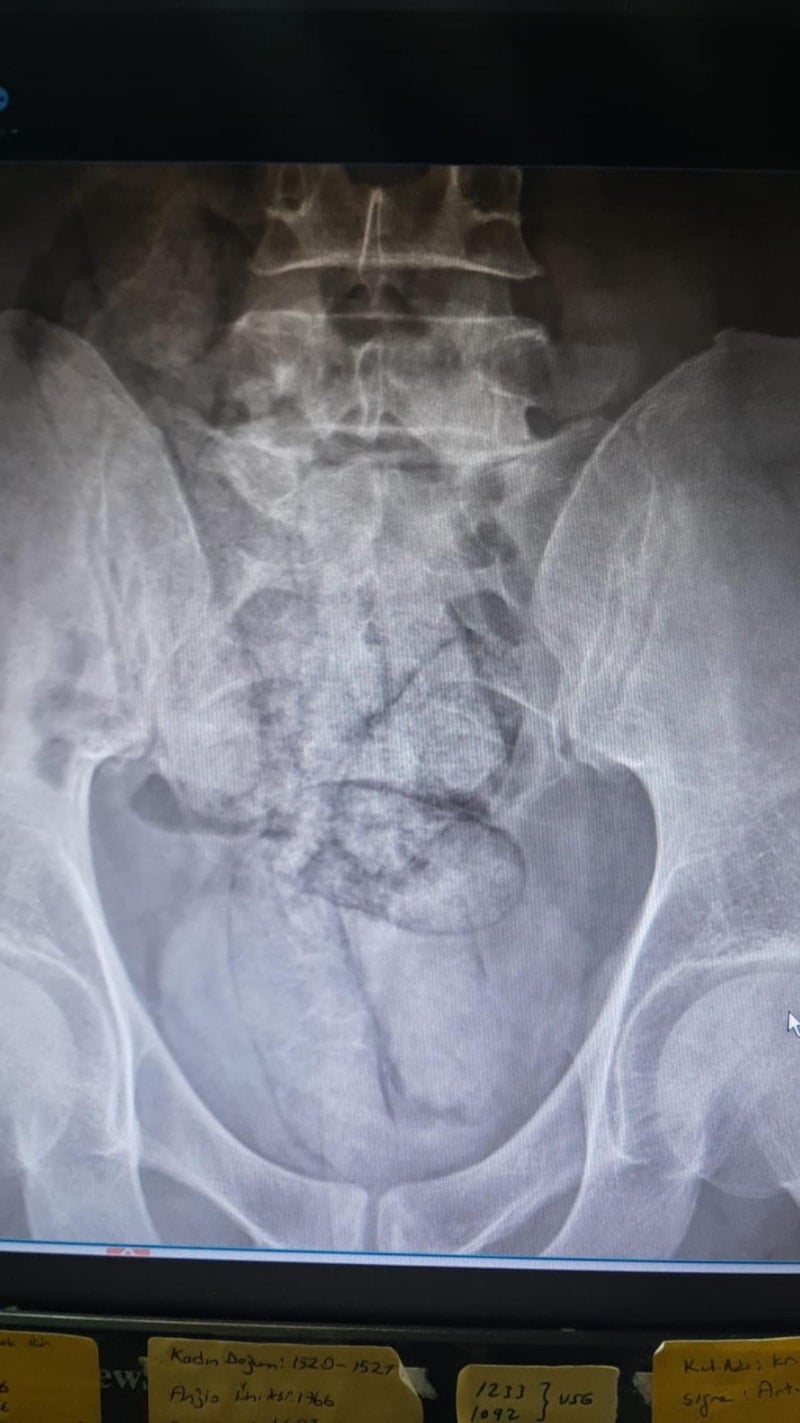

Artvin Devlet Hastanesi’ne götürülen F.R.’nin yapılan tomografisinde, bağırsaklarında 10 paket uyuşturucu madde taşıdığı belirlendi.

Şüphelinin hayati tehlike oluşturabilecek şekilde sakladığı paketler cerrahi müdahale ile çıkarıldı.

Paketlerin içinde toplam 350 gram metamfetamin olduğu tespit edildi.